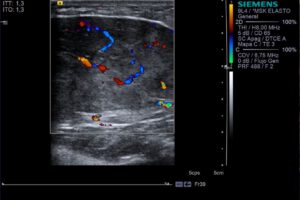

ECO Doppler de la tumoración